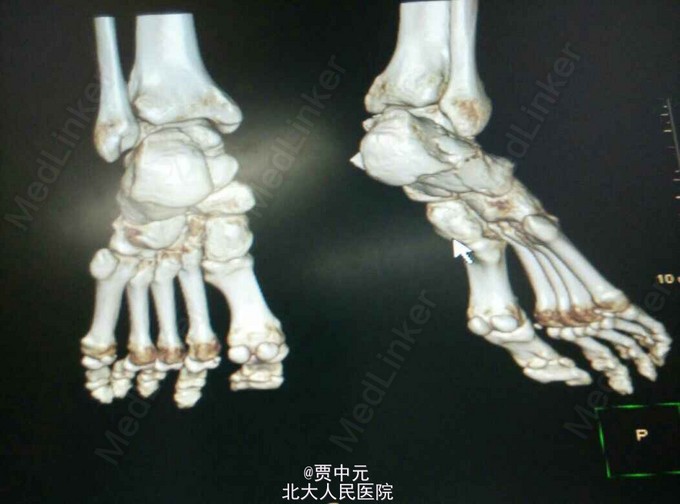

男性,31岁,主因“高处坠落伤致右足跟部疼痛,活动受限1天”于急诊以“右侧跟骨骨折”收入院。 一.病例特点 1.青年男性,高处坠落史。 2.患者约1天前自高处坠落右足着地,当时未昏迷,自觉右足肿痛,不敢活动,在当地医院拍片示:右侧跟骨骨折,为进一步手术治疗收住院。自入院来,患者无发热及胸闷憋气及腹痛症状

入院查体:右足跟部肿胀,局部皮下淤血,压痛,叩击痛,趾端血运可,足趾感觉及活动可,余肢体未见明显异常。 X线:右侧跟骨骨折(外院)

右侧跟骨骨折:高处坠落伤1天,查体:右足跟部肿胀,局部皮下淤血,压痛,叩击痛,趾端血运可,余肢体未见明显异常。 X线:右侧跟骨骨折(外院),根据外伤史,查体及X线检查,故此诊断明确

入院后考虑患者伤足局部软组织损伤重,皮肤条件欠佳,予以消肿,待皮纹征阳性后于今日在椎管内麻醉下行右跟骨骨折切开复位植骨内固定术。